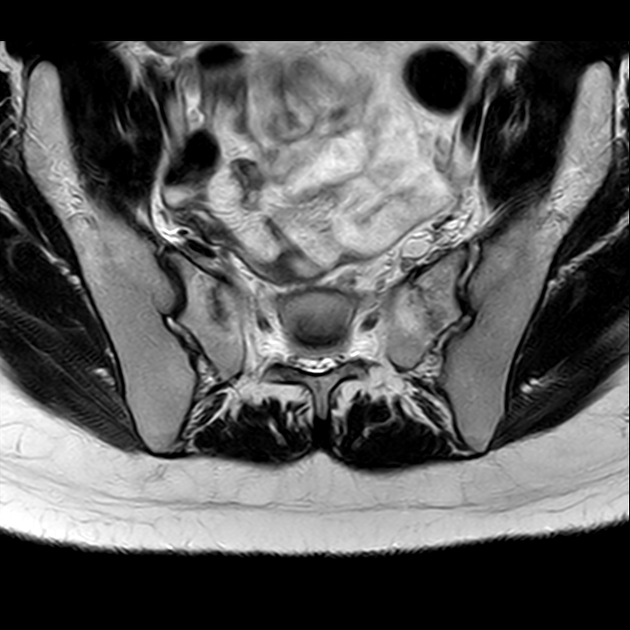

磁共振检查:

STIR

6、磁共振上可以发现骨折线周边明显的骨髓水肿,增强扫描明显强化

磁共振影像表现